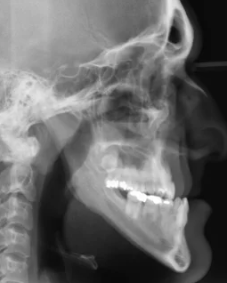

양악수술은 턱의 균형을 맞추고 기능적, 심미적인 문제를 해결하기 위해 이루어지는 복합적인 수술입니다. 수술 후에는 일정한 회복기간과 관리가 필요하며, 개인에 따라 차이가 있기는 하지만 일반적으로 몇 가지 공통적인 단계로 나누어집니다. 이 글에서는 양악수술 회복기간과 각 단계에서의 특징, 관리 방법을 폭넓게 알아보겠습니다.